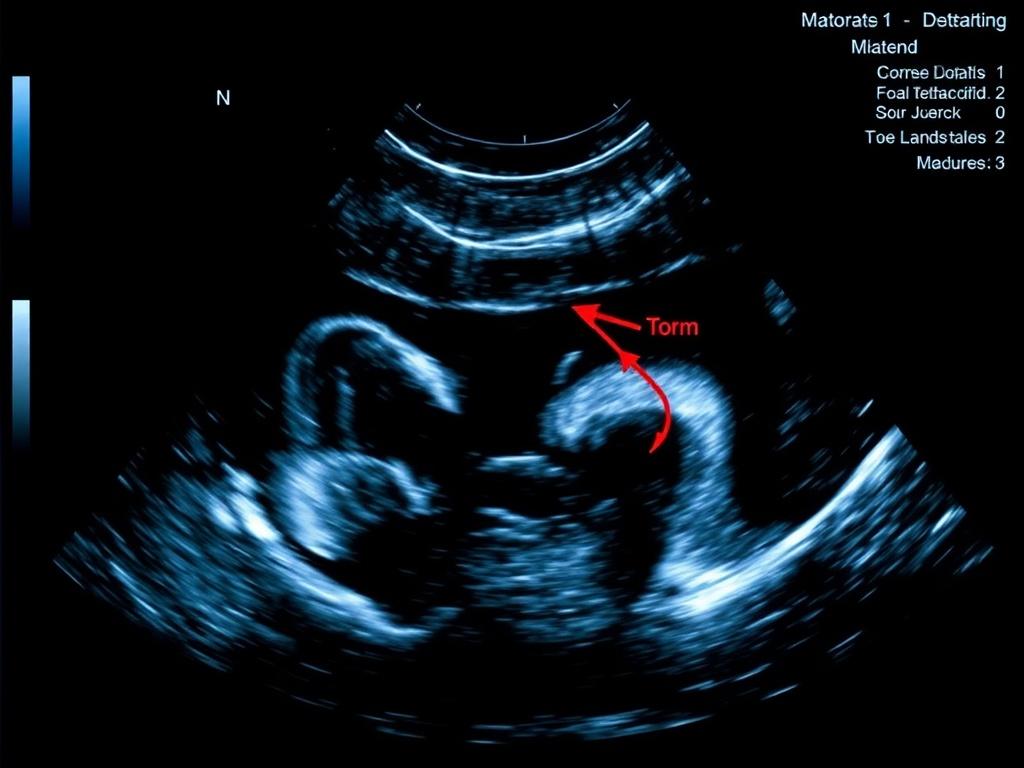

При изучении мышц и сухожилий ультразвук показывает структуру волокна и позволяет оценить integrity ткани. Травмы, разрывы сухожилий, бурситы и локальные скопления жидкости хорошо видны на сонограммах.

Динамическое сканирование — сильная сторона в этой области. Проследить сокращение мышцы, смещение сухожилия при движении суставов, увидеть, как изменяется роль фасций — эти вещи нельзя понять одинаково глубоко по снимкам КТ или МРТ.